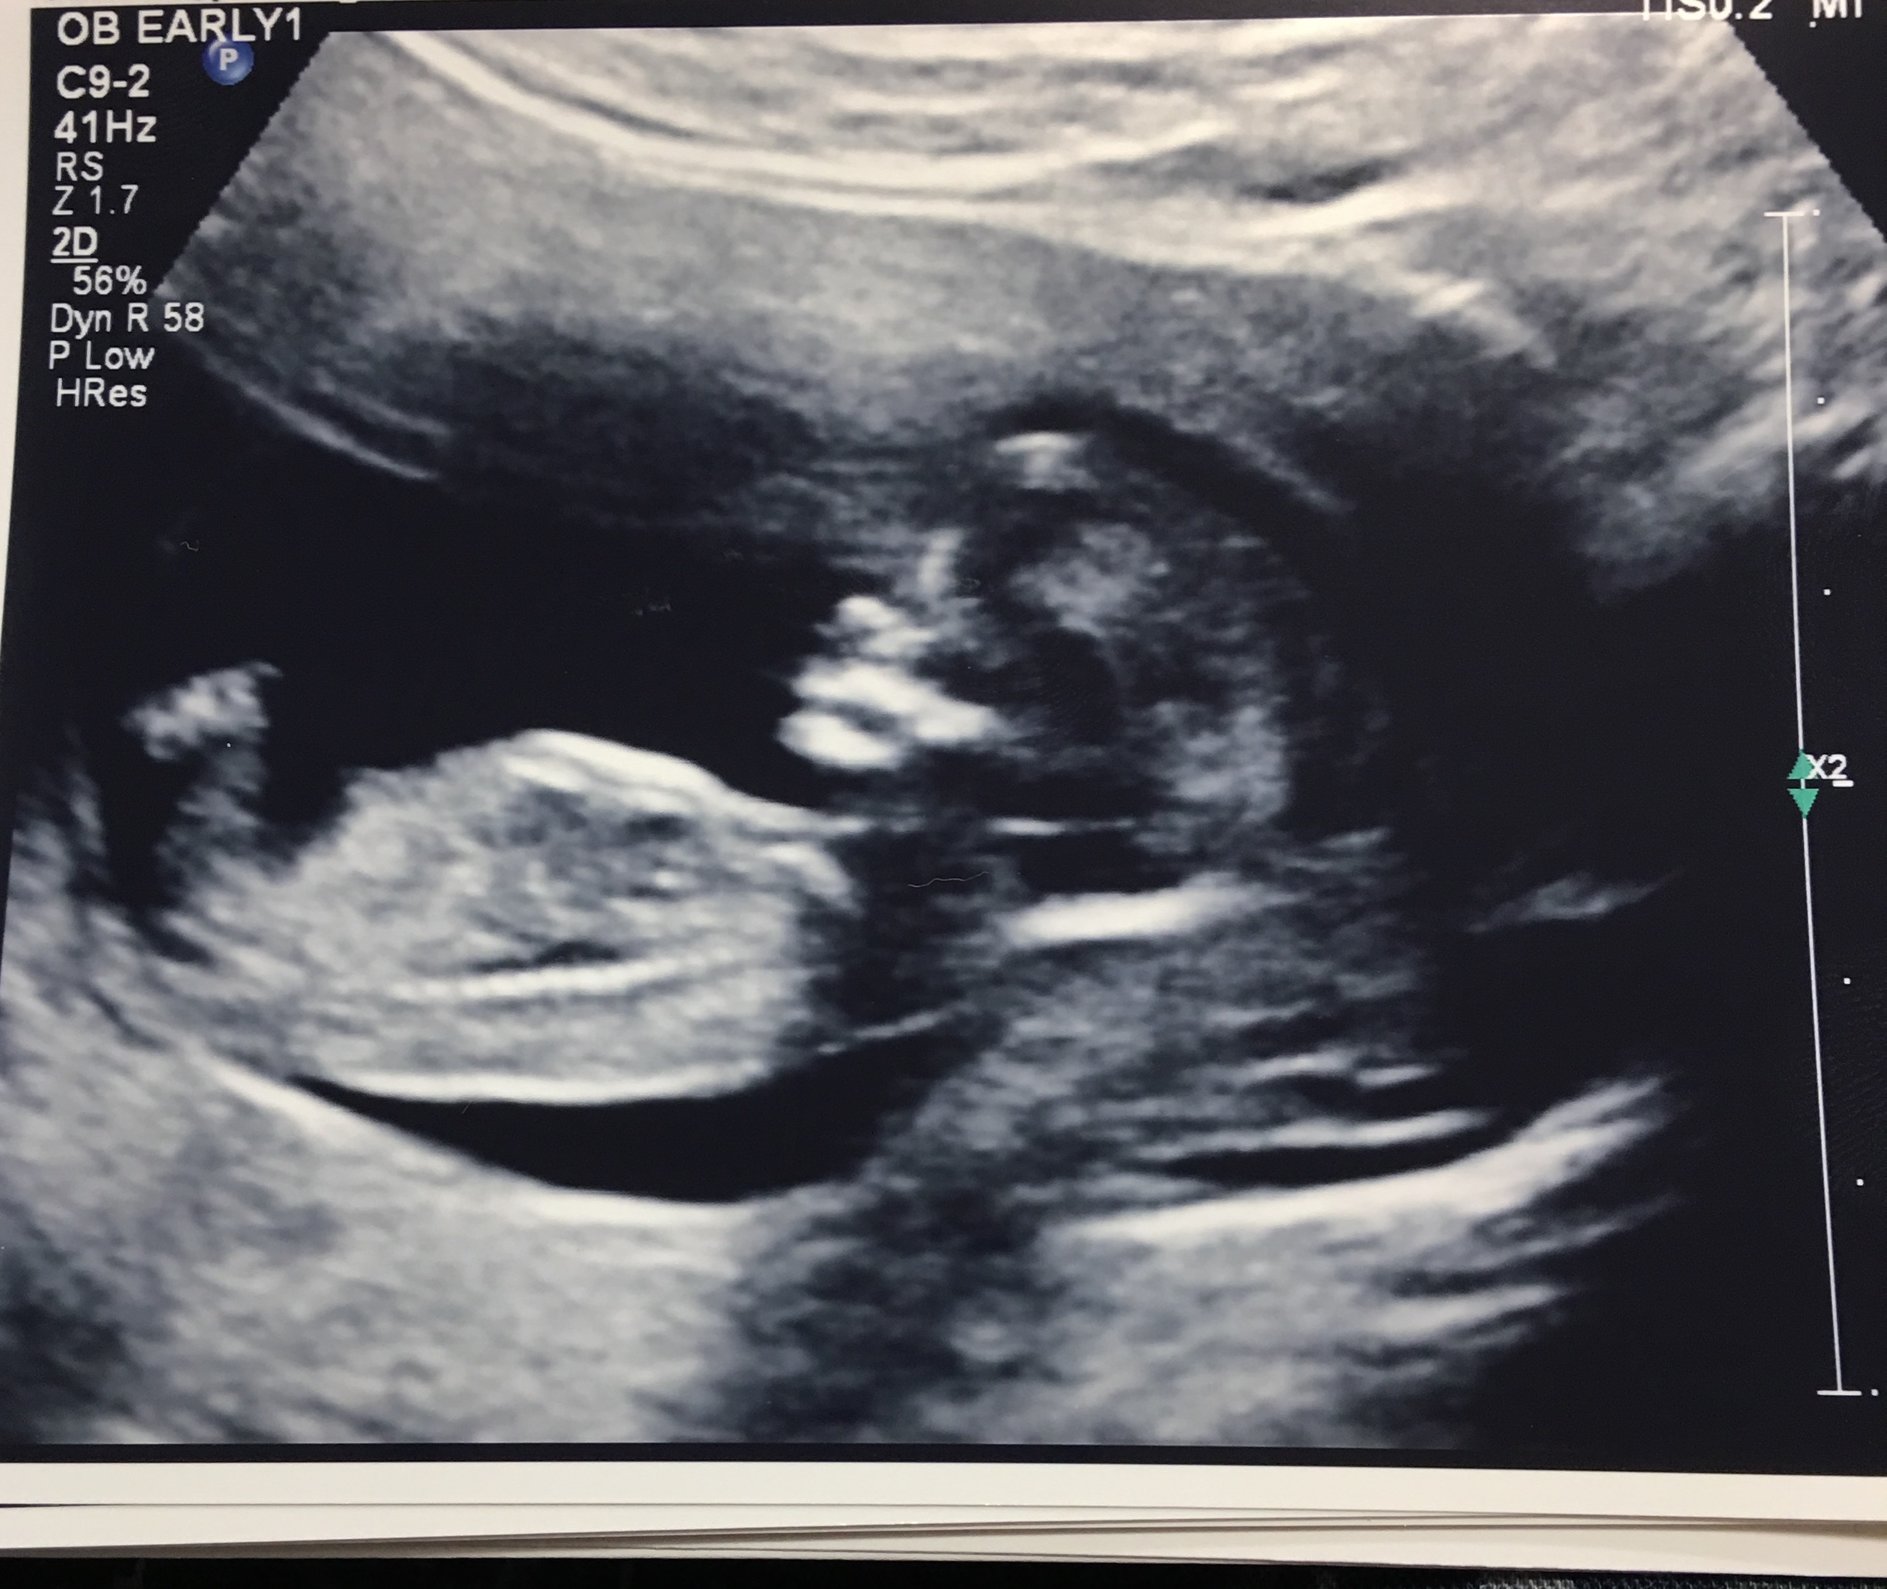

9w5d measuring at 10w1d. HR 167. Our little gummy bear was wiggling all around and even kicked for us quite a bit. They also kept bringing their hand to their mouth...it's so crazy to see what's happening inside! It's starting to look like a real human.

Saw little jellybean for the first time Friday afternoon. Measure 9w3 and got an official due date of June 20. So relieved and happy to sneak a peak of this little guy or gal.